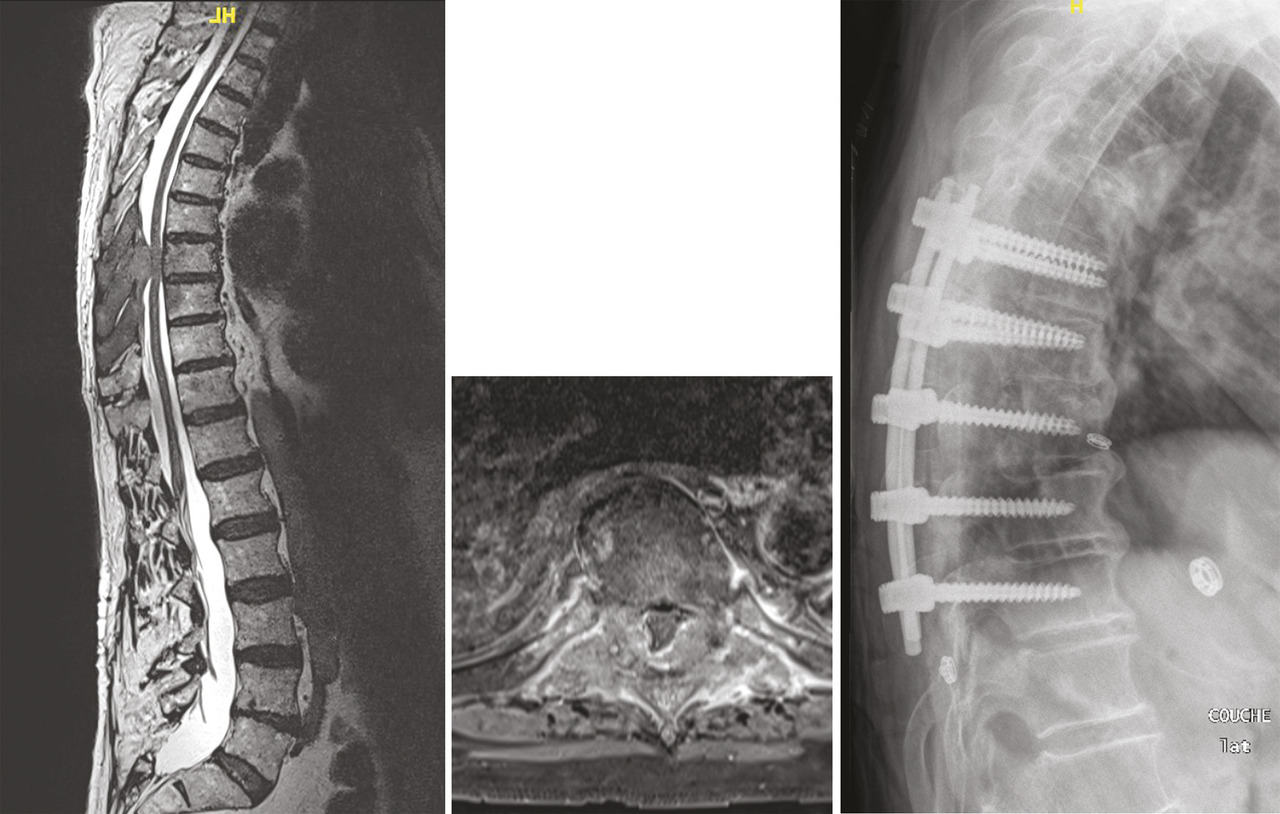

L’ostéosynthèse moderne permet de fixer solidement le rachis. Les vis pédiculaires,5 au besoin aidées par le cimentage du corps vertébral, sont utilisées couramment dans tous les services de chirurgie du rachis. L’immobilité obtenue est le meilleur moyen de lutter contre la douleur.6 Mais l’ostéosynthèse permet aussi la réduction de la déformation dans les trois plans de l’espace (fig. 3 et 4 ). L’équilibre rachidien restitué facilite la reprise de la marche et redonne une vie plus facile au patient qui a subi dans son dos le poids des ans.7 L’ostéosynthèse est solide et permet un lever immédiat en règle générale sans contention externe. Une greffe osseuse pérennise le montage le protégeant d’un démontage ou d’une fracture du matériel.

L’ostéosynthèse moderne permet de fixer solidement le rachis. Les vis pédiculaires,5 au besoin aidées par le cimentage du corps vertébral, sont utilisées couramment dans tous les services de chirurgie du rachis. L’immobilité obtenue est le meilleur moyen de lutter contre la douleur.6 Mais l’ostéosynthèse permet aussi la réduction de la déformation dans les trois plans de l’espace (